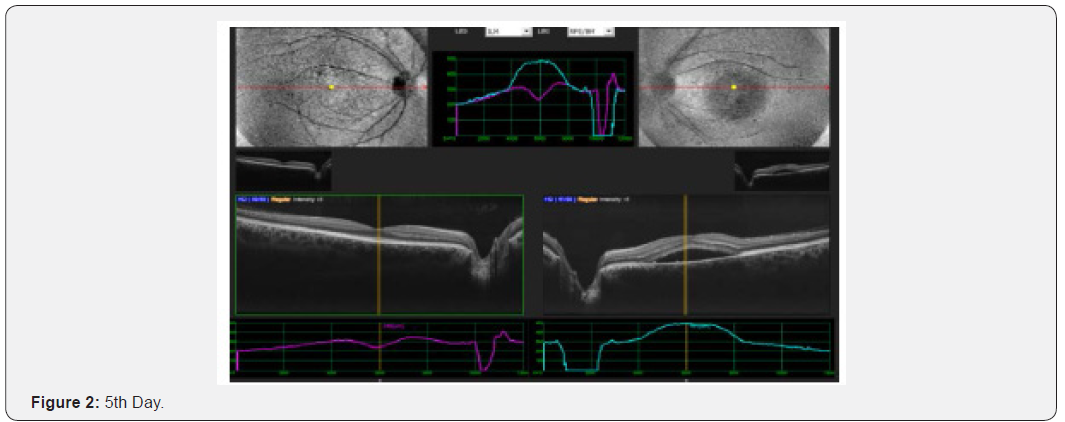

Results: This interventional study includes 21 patients who were diagnosed as acute CSC and followed from the day of presentation to 30th day. All 21 patients were undergoing intervention by using topical bromfenac eye drop, one drop twice daily for 30 days. Macular thickness and visual acuity recorded from the day of presentation up to 30th day. (Table 6) shows all changes before and after treatment and (Figure 1-4) shows early resolution of sub-macular fluid in one of these patients treated with topical bromfenac eye drops (one drop twice daily). In group 1 the macular thickness (CFT) improve from 422-485 microns at onset to 317-382 microns on 5th day becomes 246-295 on 10th day while 210-226 on 30th day. Vision improved from 0.4 to 0.7 at 5th day, improved to 0.8 on 10th day and remained same on 30th day. In group 2 the CFT reduced from 535-565 microns to 401-440 microns on 5th day becomes 318310 on 10th day and on 30th day it was 221-232 microns with improvement in visual acuity which was 0.2 at onset to 0.6 at 5th day, 0.7 at 10th day and improved to 0.8 on 30th day. In group 3 the CFT reduced from 657-722 microns to 456-469 microns on 5th day, 259-366 microns on 10th day while 206-227 microns on 30th day. Visual acuity improved from CF at onset to 0.4 on 5th day, 0.6 on 10th day and improved to 0.7 on 30th day. Conclusion: This, simple, safe, affordable and easily available treatment modality in all parts of the world with early rehabilitation of acute CSC patients.

This interventional retrospective as well as prospective study includes 21 patients who were diagnosed as acute CSC and followed from the day of presentation to 30th day. All 21 patients were undergoing intervention by using topical bromfenac eye drop, one drop twice daily for 30 days. Macular thickness and visual acuity recorded from the day of presentation up to 30th day. (Table 6) shows all changes before and after treatment and (Figure 1-8) shows early resolution of sub-macular fluid in one of these patients treated with topical bromfenac eye drops (one drop twice daily). In group 1 the macular thickness (CFT) improve from 422-485 microns at onset to 317-382 microns on 5th day becomes 246-295 on 10th day while 210-226 on 30th day. Vision improved from 0.4 to 0.7 at 5th day, improved to 0.8 on 10th day and remained same on 30th day. In group 2 the CFT reduced from 535-565 microns to 401-440 microns on 5th day becomes 318-310 on 10th day and on 30th day it was 221-232 microns with improvement in visual acuity which was 0.2 at onset to 0.6 at 5th day, 0.7 at 10th day and improved to 0.8 on 30th day. In group 3 the CFT reduced from 657-722 microns to 456-469 microns on 5th day, 259-366 microns on 10th day while 206-227 microns on 30th day. Visual acuity improved from CF at onset to 0.4 on 5th day, 0.6 on 10th day and improved to 0.7 on 30th day.